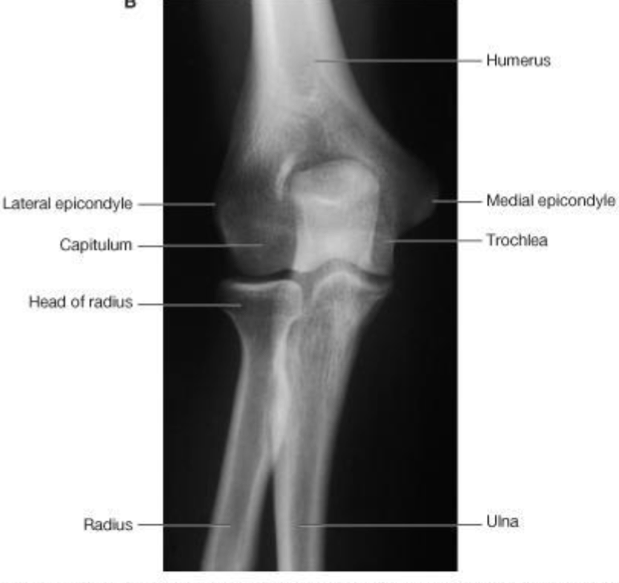

Elbow Joint

Humerus

Medial epicondyle

Lateral epicondyle

Capitulum

Trochlea

Radius

Ulna